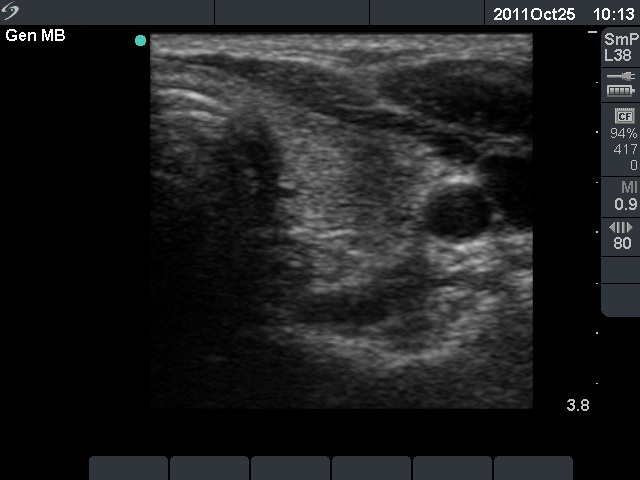

The relapse of de Quervain's thyroiditis in the contralateral lobe is a very frequent finding but not one year after the appearance of the disease. We supposed that the immunological changes during and after pregnancy explained the relatively late relapse of the disease.

The ultrasound pattern of de Quervain's thyroiditis and that of papillary cancer are very similar: a hypoechogenic lesion with blurred borders are found in both cases. They differ in vascularization statistically but the vascular pattern has only limited practical significance. In the acute phase of de Quervain's thyroiditis the vascularization is generally decreased but even in this case the situation was the opposite. The finding of not one but multiple hypoechogenic areas favored the possibility of subacute thyroiditis.